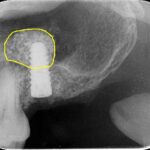

レントゲンは70代男性。本日、無事にインプラント上にジルコニアの歯が入った。サイナスリフトをラテラルスリット法でおこない、骨造成をし、インプラント治療をやらせていただいた。

入れ歯と比べるとインプラント治療の咀嚼機能の回復は著しい。しかし、大臼歯部は骨の厚みがなく、インプラント治療をあきらめざるを得なかった患者さんも多い。

サイナスリフト法インプラント治療は骨の厚みがなくインプラント治療をあきらめざるを得なかった患者さんにもとても有効な術式である。しかもラテラルスリット法は従来より侵襲や術後の腫れが少ない手術法である。